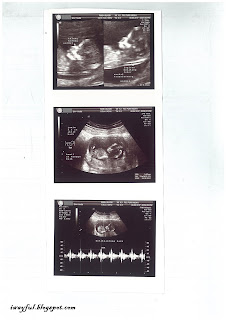

Istri kembali di-USG, kondisi janinnya tetap baik dan tidak ada perdarahan lagi. Karena ini sudah memasuki minggu ke-12, dr. Budi juga mengecek ketebalan lapisan belakang leher janin (nuchal translucency / NT) untuk mengetahui probabilitas terjadinya down syndrome, nilai NT-nya 0,72mm yang berarti normal. Tulang hidung bayi kami juga dilihat dan hasilnya normal.

| USG janin usia 12w1d ukuran 5,52 cm |

| USG 4 dimensi |

| kesimpulan hasil USG |